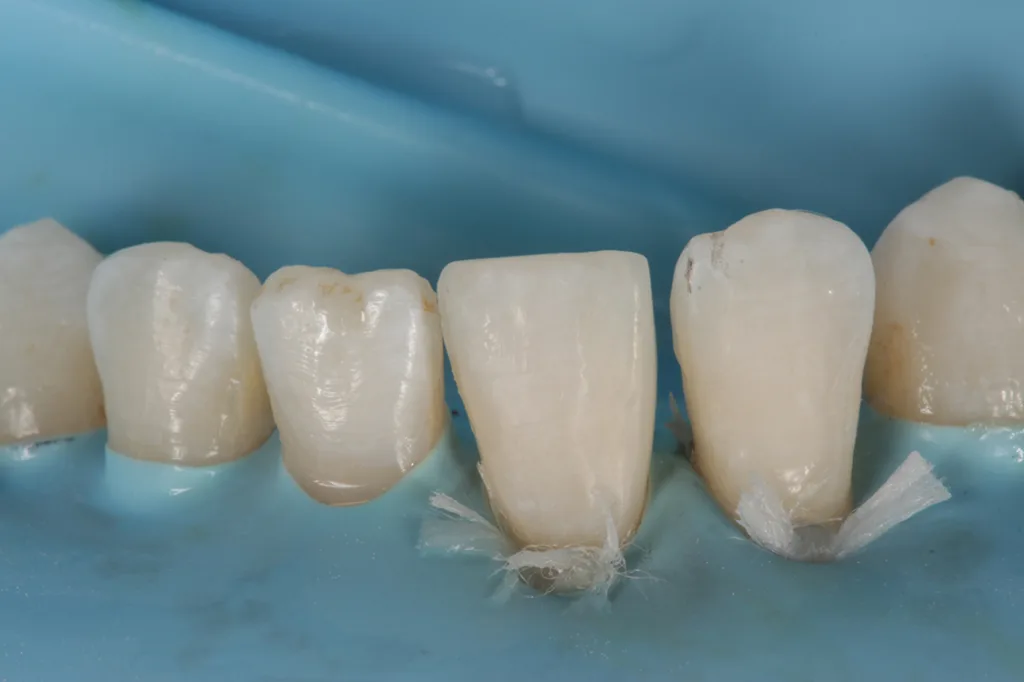

Nach Befundaufnahme und professioneller Zahnreinigung wurde ein CMD-Kurzscreening durchgeführt und ein Fotostatus erstellt. Ein intraorales Mock-up [2] wurde auf Wunsch der Patientin und aus Kostengründen nicht angefertigt. Definitive Versorgung Adhäsivrestaurationen mit Komposit an 31/32 zum Schluss des Diastema laterale (Abb. 3 bis 9).